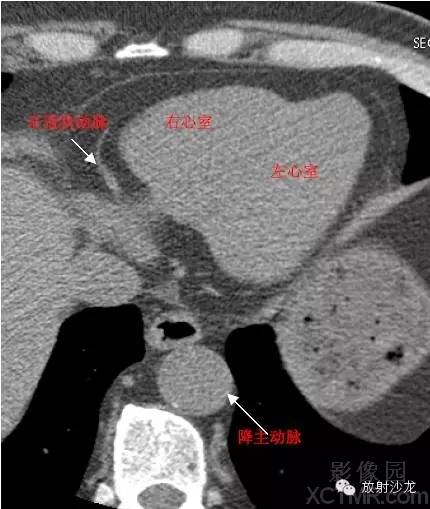

LV -Left Ventricle左心室

RV -Right Ventricle右心室

D. Aorta-Descending Aorta降主动脉

RCA -Right Coronary Artery 右冠状动脉